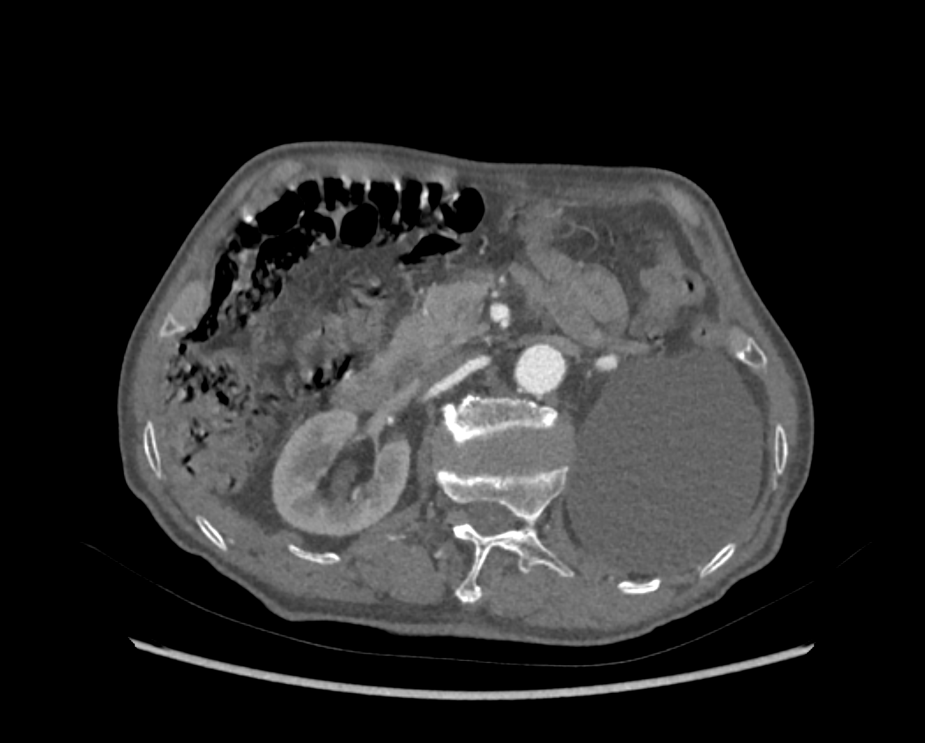

患者为74岁男性,2年前活动后出现胸闷、气短,休息后可以缓解。2021年5月症状加重,我院超声心动图提示:主动脉瓣反流(重度)、二尖瓣反流(重度),二尖瓣后叶脱垂(P2区)。左肾巨大囊肿,肾实质几不可见,左肾几无功能。

左肾巨大囊肿,压迫肾实质

患者老年男性,心衰症状明确,一般情况较差,肾脏储备功能差,外科手术高危,STS评分15.6%。其合并多瓣膜病,主动脉重度关闭不全及二尖瓣退行性重度反流均有介入手术指征,经讨论,拟先行TAVR术,术后最佳药物治疗,随访二尖瓣反流及患者心力衰竭变化情况,根据情况择期行二尖瓣钳夹。